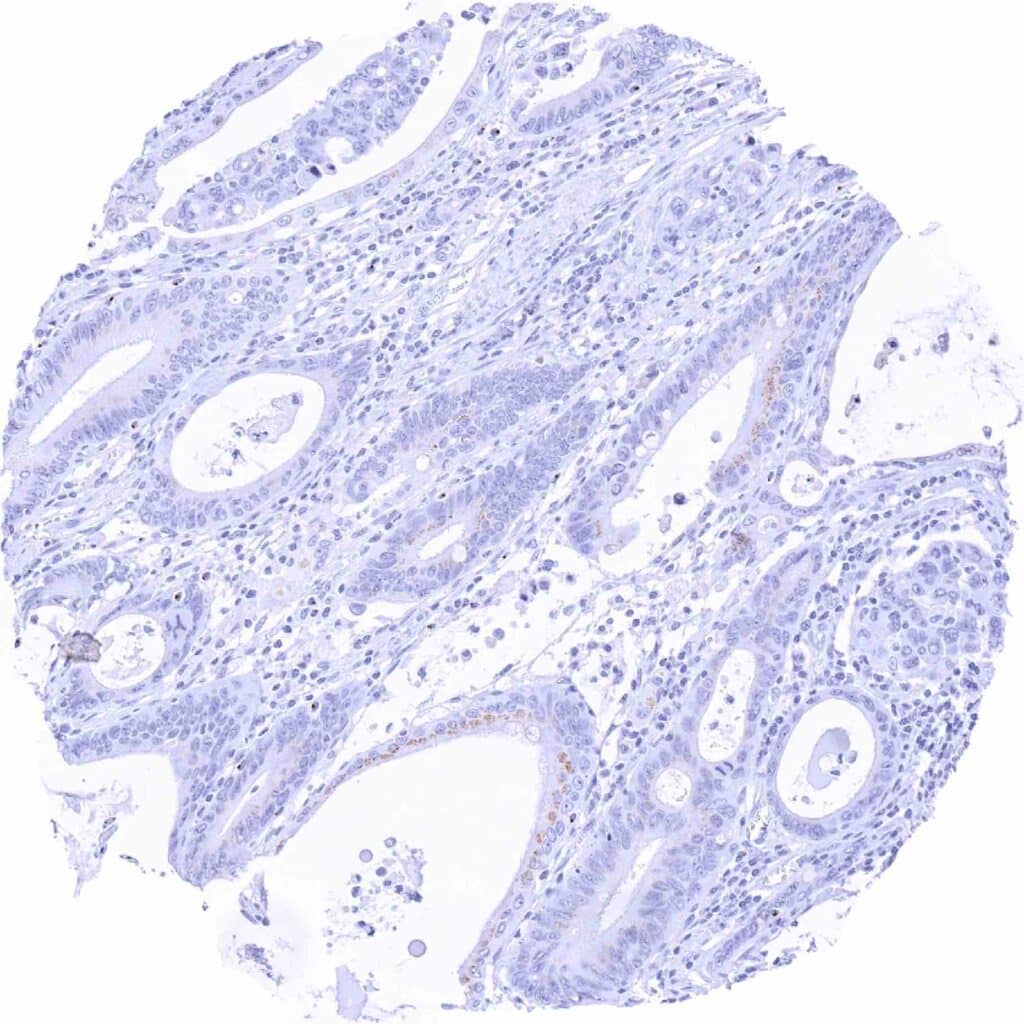

Pancreas – Ductal adenocarcinoma showing moderate granular perinuclear Prostein staining of neoplastic cells